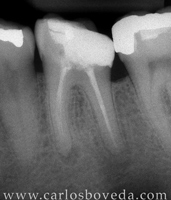

Retratamiento de Conductos en Una Sesión - (formato Quicktime)